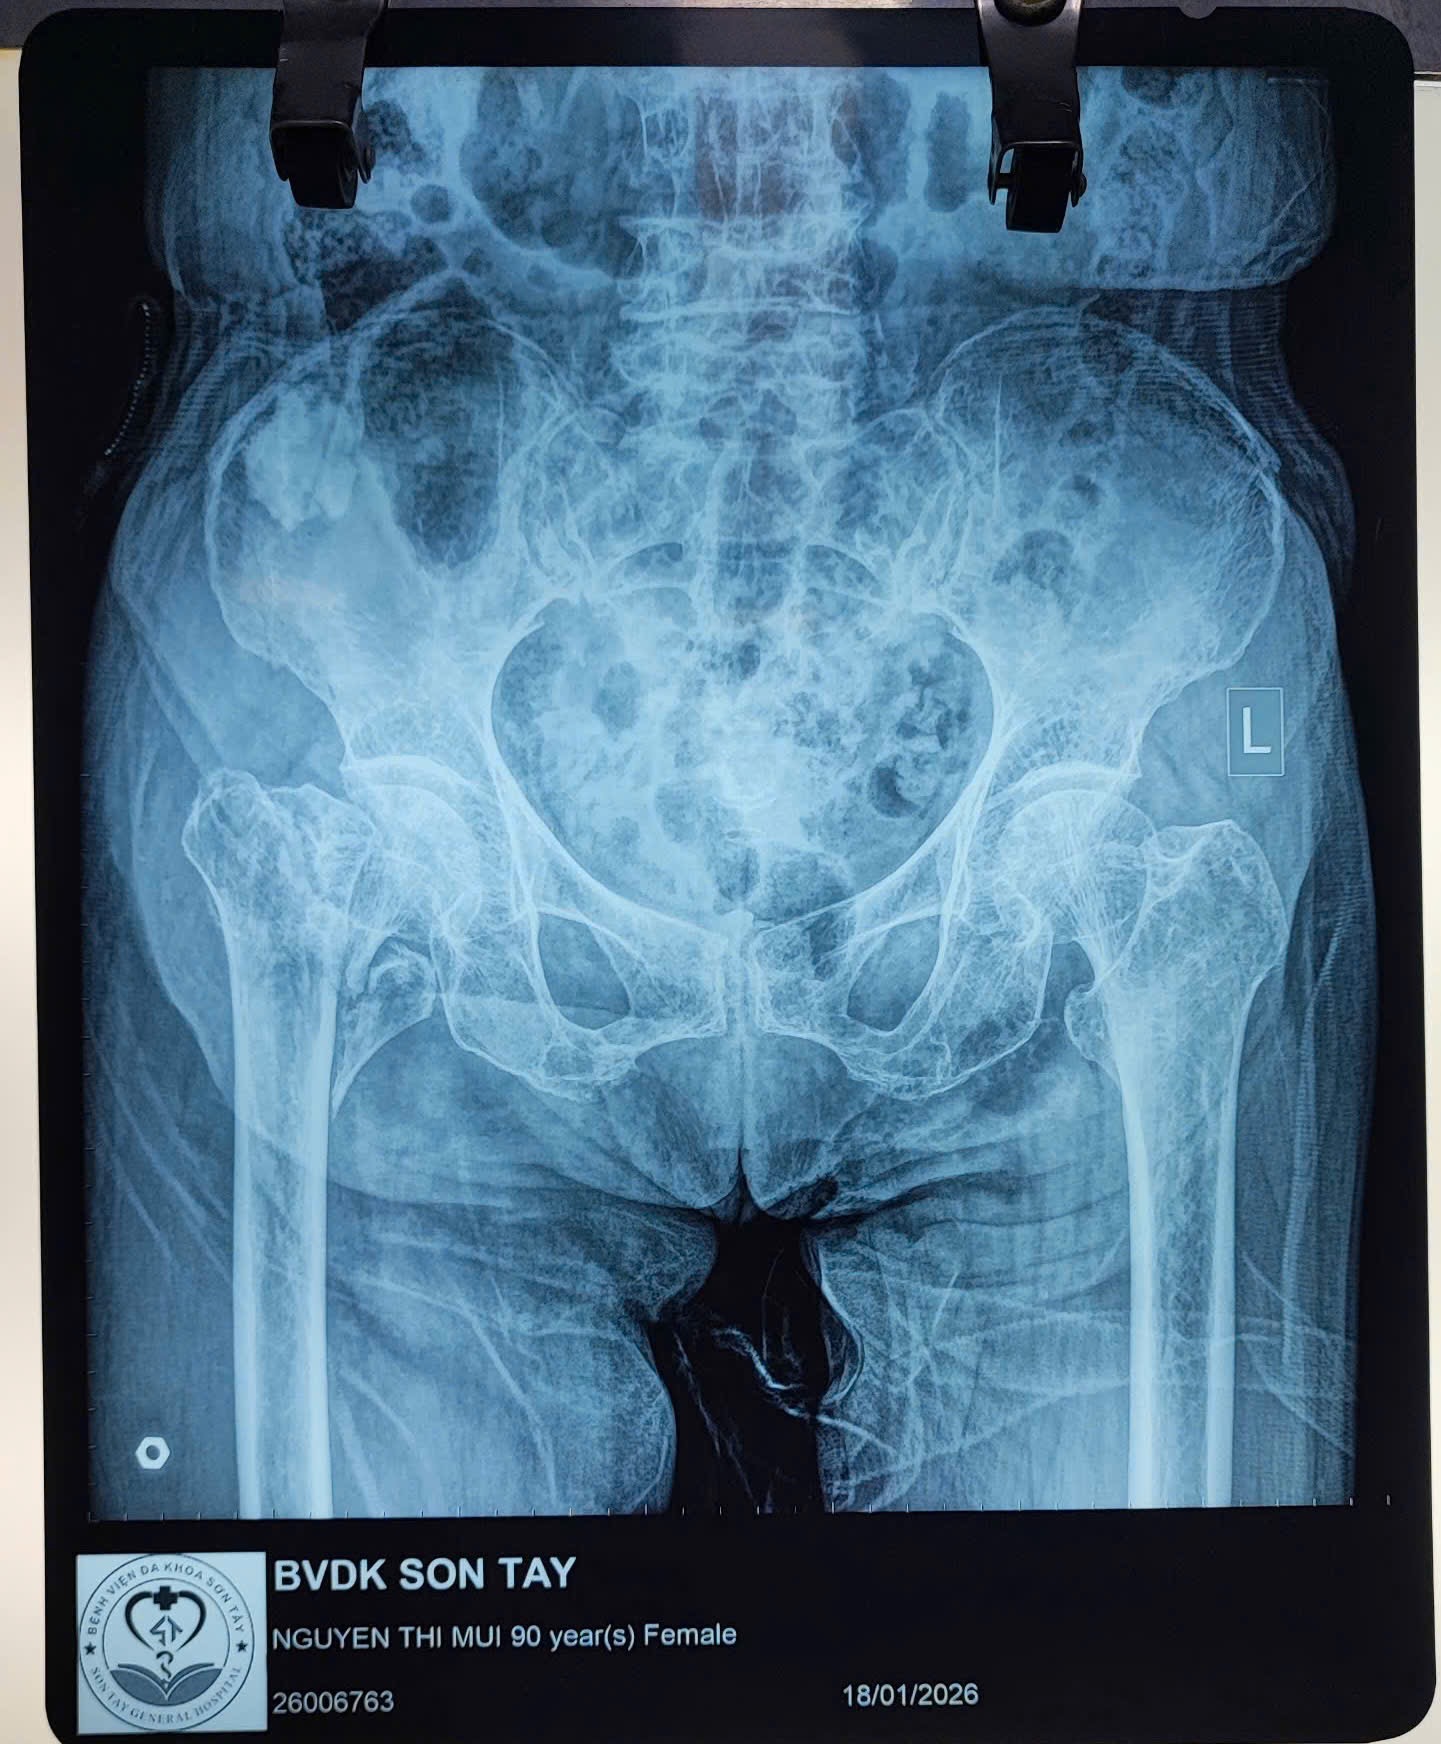

🩺 Bệnh nhân nhập viện trong tình trạng gãy phức tạp vùng liên mấu chuyển/cổ xương đùi phải trên nền loãng xương nặng, kèm nhiều bệnh lý nội khoa như tăng huyết áp, suy tim. Theo người nhà, bệnh nhân bị ngã tại nhà, đau nhiều vùng háng – đùi phải, không thể đi lại.

📸 Kết quả X-quang và CT cho thấy tổn thương phức tạp đầu trên xương đùi, nguy cơ cao nếu điều trị bằng phương pháp kết hợp xương thông thường. Sau hội chẩn liên chuyên khoa (Ngoại Chấn thương, Gây mê hồi sức, Nội tim mạch), ê-kíp điều trị thống nhất chỉ định thay khớp háng bán phần nhằm giúp bệnh nhân giảm đau nhanh, vận động sớm, hạn chế biến chứng do nằm lâu.